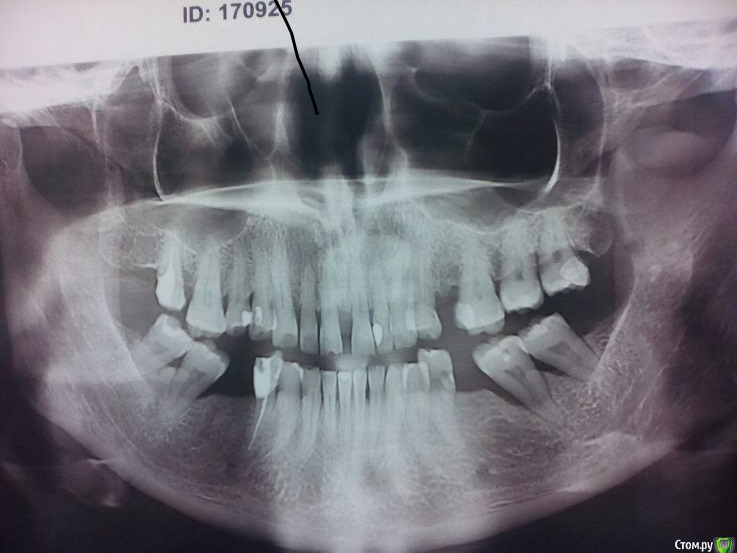

Danger Опубликовано 7 мая, 2017 Поделиться Опубликовано 7 мая, 2017 Обратилась пациентка с целью протезирования зубов жевательного сегмента. Хочет безметалловую конструкцию. Попросил сделал орто. Не знаю как поступить с 37 и 47 зубами. Слегка подвижны. НА такие ставить мост безумство? Ссылка на комментарий

Danger Опубликовано 7 мая, 2017 Автор Поделиться Опубликовано 7 мая, 2017 Ну если она хочет безметаловую конструкцию,как вы пишите,то сделайте безметалловые коронки с опорой на импланты.Или вы ей хотите 35-37 мостик циркониевый сделать?имплантации не будет.Она пришла с желанием сделать мост такой протяженности,хочет безметалловый. Меня смущает не материал из которого он будет сделан, а зубы на которые он фиксируется.До орто да, думал делать 45 47 мост. Ссылка на комментарий

chervoncevdaniil Опубликовано 7 мая, 2017 Поделиться Опубликовано 7 мая, 2017 Так материл тут и не причем,речь об опорных зубах дистальных.45-47 тоже не особо,учитывая что 45 одна большая пломба,а 47 с убылью костной ткани больше чем в половину корня Ссылка на комментарий

алекс 100 Опубликовано 12 мая, 2017 Поделиться Опубликовано 12 мая, 2017 Такие моляры можно и пролечить-похоже что по одному огромному каналу в каждом. Ссылка на комментарий

valen Опубликовано 17 мая, 2017 Поделиться Опубликовано 17 мая, 2017 (изменено) )) Конечно можно, тем более если по одному большому каналу в каждом нижнем моляре.., и еще вкладками однокорневыми укрепить, диоксидом закрыть.... ...и сваливать из страны Плохо видно, но, по моему, это классические си-шейпы. Как раз из тех , в которых, куда не плюнь - дейнджер-зона. Пациентка может хотеть многого, но у врача руководством являются показания и, особенно, противопоказания. Изменено 17 мая, 2017 пользователем valen Ссылка на комментарий